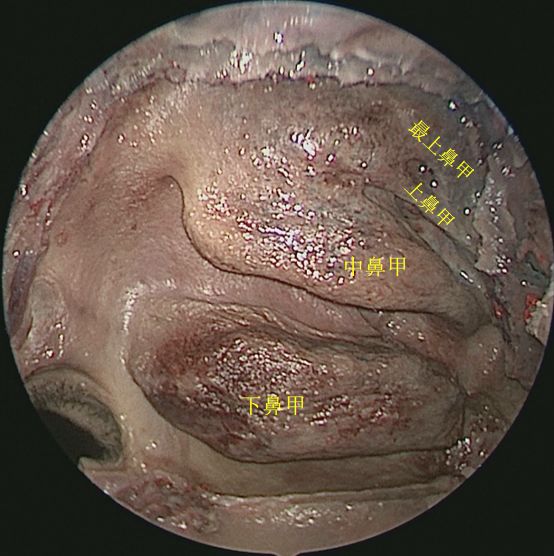

侧方观察右侧鼻腔侧壁结构

45度角观察右侧鼻腔侧壁

切除右侧中鼻甲后观察右鼻腔侧壁